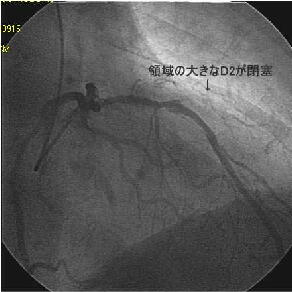

Crush���KBT.

|

|

|